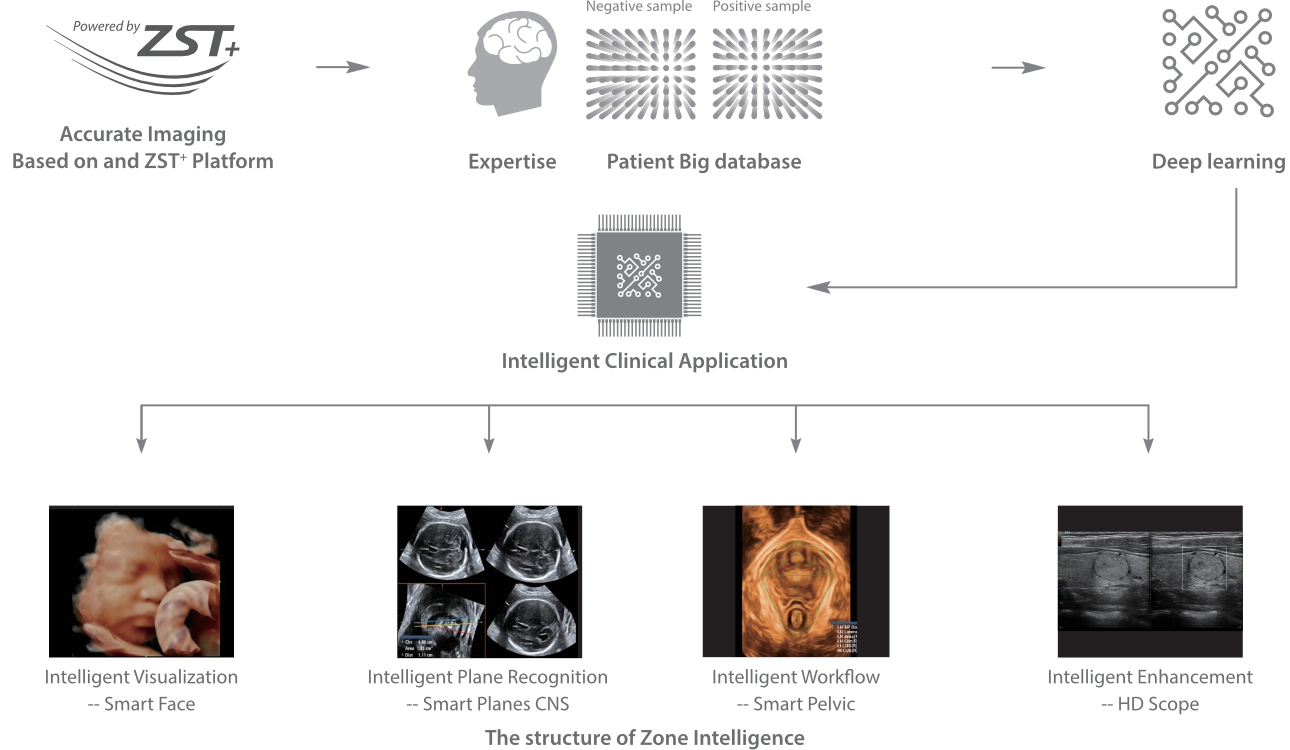

Fin dalla sua fondazione Mindray esplora continuamente nuovi modi per migliorare l'affidabilit├Ā diagnostica. Equipaggiata con la pi├╣ rivoluzionaria tecnologia ZONE Sonography?, la nuova piattaforma ZST+ di Resona 7 porta la qualit├Ā dell'immagine ecografica ad un livello superiore con l'acquisizione per zone e l'elaborazione dei dati canale.

Oltre alla qualit├Ā delle immagini di livello eccellente, Resona 7 migliora anche le capacit├Ā di ricerca clinica il rivoluzionario V Flow per la valutazione emodinamica vascolare, e l'acquisizione piani pi├╣ intelligente dal set di dati 3D per la diagnosi del sistema nervoso centrale fetale. Combinando il pi├╣ intuitivo funzionamento multi-touch basato su gesti e tutte le caratteristiche cliniche essenziali, Resona 7 sta veramente portando nuove tendenze nellŌĆÖinnovazione dellŌĆÖecografia.